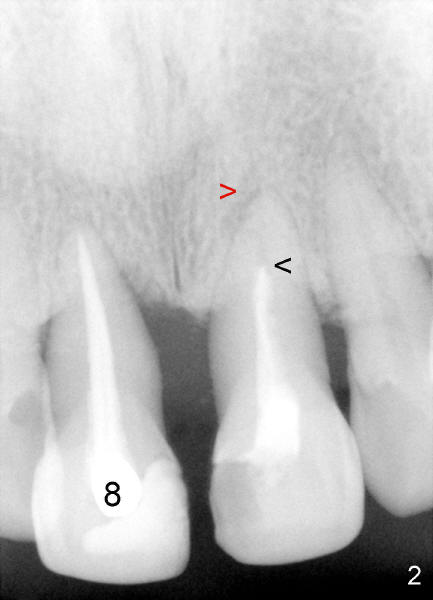

Fig.2 pre-op: #8 endo-perio disease, nonsalvageable; #9 RCT short fill (black arrowhead) with periapical radiolucency (red arrowhead). Fig.3: 15 months after RCT retreat (arrowhead), the periapical radiolucency of #9 isappears; 12 months after extraction of #8, Bicon 4.5x8 mm implant placed (I). Return to original article